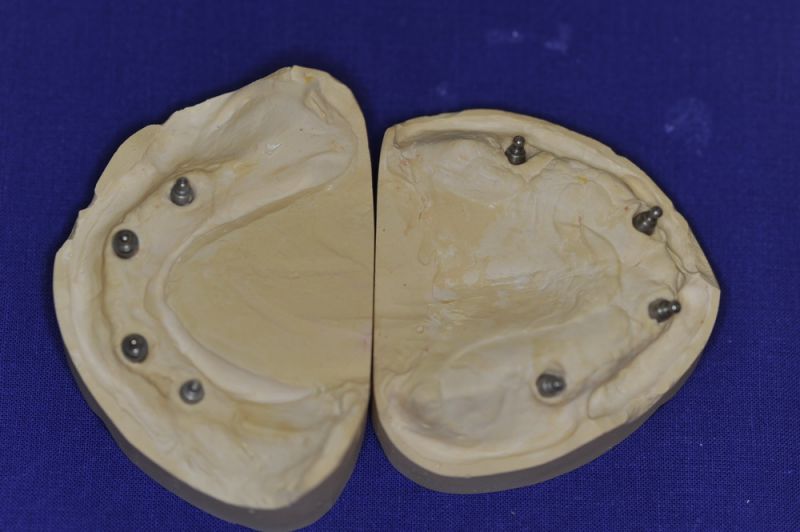

Das Einkleber der O-Ring-Abutments, etwas euphemistisch als "chair-side" beschrieben entwickelte sich zu einem schweißtreibenden Abendvergnügen.